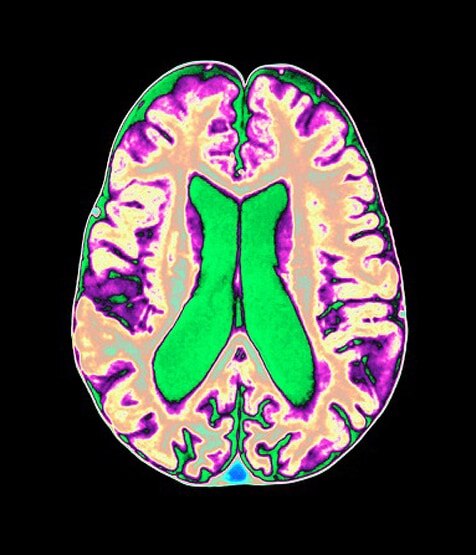

आमतौर पर ये माना जाता है कि कोरोना वायरस का ज्यादातर असर फेफड़ों और शरीर की श्वास प्रणाली पर होता है. लेकिन अब दिमाग पर भी इसके दुष्प्रभाव देखने को मिल रहे हैं. (फोटोः AFP)

कनाडा की वेस्टर्न यूनिवर्सिटी के न्यूरोसाइंटिस्ट एड्रियन ओवेन ने बताया कि इस समय सबसे बड़ी चिंता की बात ये है कि कोरोना वायरस से लाखों लोग पीड़ित हैं. अगर एक साल के अंदर 1 करोड़ लोग भी इस बीमारी से रिकवर हो जाते हैं तब भी उनके शरीर में कई बीमारियां घर बना लेंगी. उनमें से दिमागी समस्याएं भी प्रमुख होंगी. इससे उनका डेली रूटीन का काम खराब होगा. (फोटोः AFP)